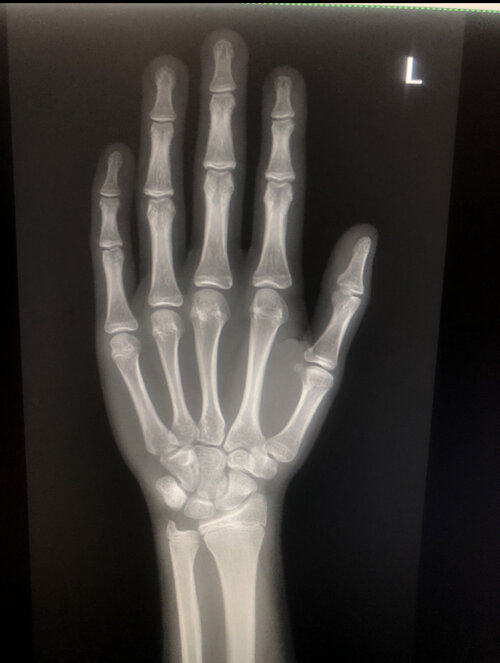

I got an xray of my growth plates today and they were fused at 15 total suacife fuel

:feelsrope::feelsrope: and the doctor told me to get ur knees and pelvic to help me cope with it 168cm ans ugly as fuck never gotten this much ropefuel and i had js gotten like 2mkmth o

• IMG_2026.jpeg

IMG_2026.jpeg